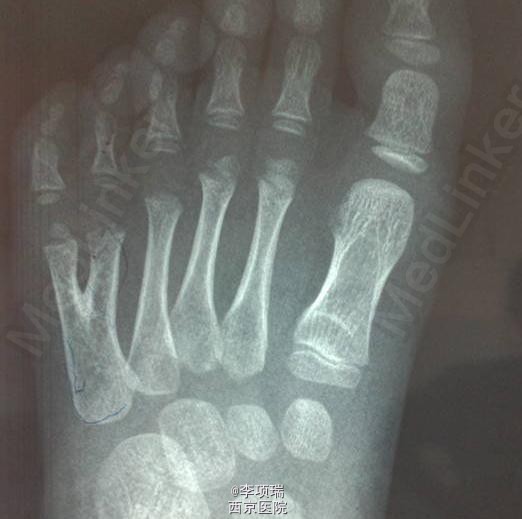

脚趾多趾病例1例

多趾

5岁女童,左足第五趾多趾,行多趾切除+肌腱移位术。